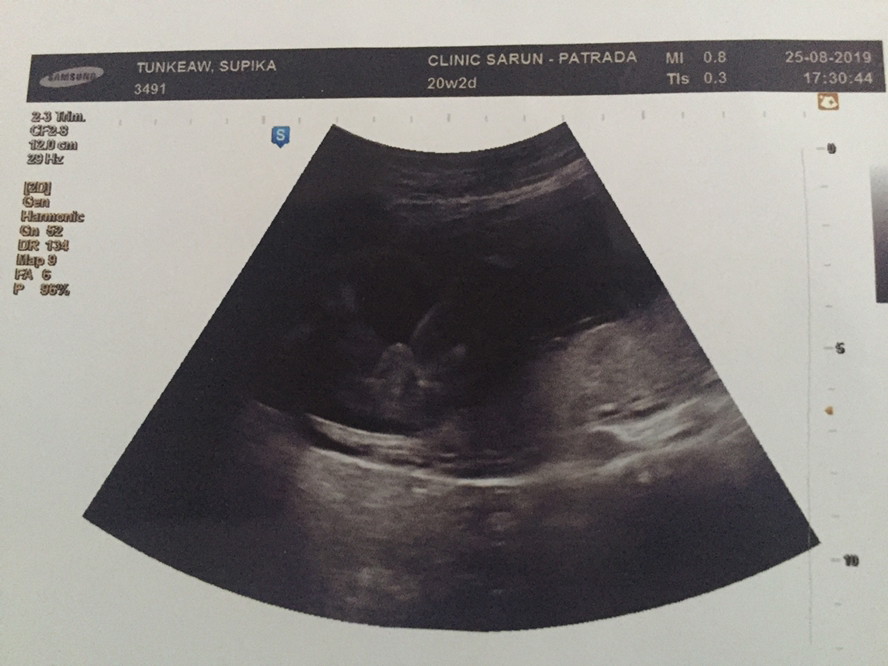

บ้านนี้มีไข่คะ

ดูให้หน่อยค่ะ